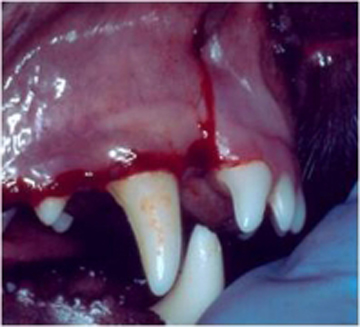

La cirugía en cavidad oral es una de las áreas más socorridas en odontología veterinaria. La extracción dental es el procedimiento que más se utiliza en México sobre todo en perros. La enfermedad periodontal es la causa más común de indicación para la extracción dental, siguiéndole las fracturas dentales por traumatismo y los problemas pulpares. La forma y disposición de las raíces en perros, gatos y otras especies carnívoras, hacen de la extracción un área muy difícil en casos de no existir enfermedad periodontal. En perros los problemas más comunes de extracción dental es de que las raíces de los dientes bi radiculares y tri radiculares están divergentes, por lo que siempre se tienen que seccionar quirúrgicamente las coronas hacia la furcación con el fin de separar las raíces para su extracción como si fueran dientes de una sola raíz aundo con el levantamiento de un colgajo mucoperióstico y ostectomía en la zona vestíbulo cervical. Los caninos es otro problema ya que el tercio medio de la raíz es más ancho que el tercio cervical, por lo que para su extracción se realiza la ostectomía de la cortical externa previo levantamiento de un colgajo mucoperióstico. La extracción de dientes en gatos presenta un problema básicamente y es que sus raíces son muy pequeñas y delgadas por lo que si no se tiene cuidado y paciencia regularmente se fracturan. La mayoría de casos que atendemos en nuestra práctica en gatos es la de restos radiculares por fracturas dentales iatrogénicas.

Extracción de un canino superior